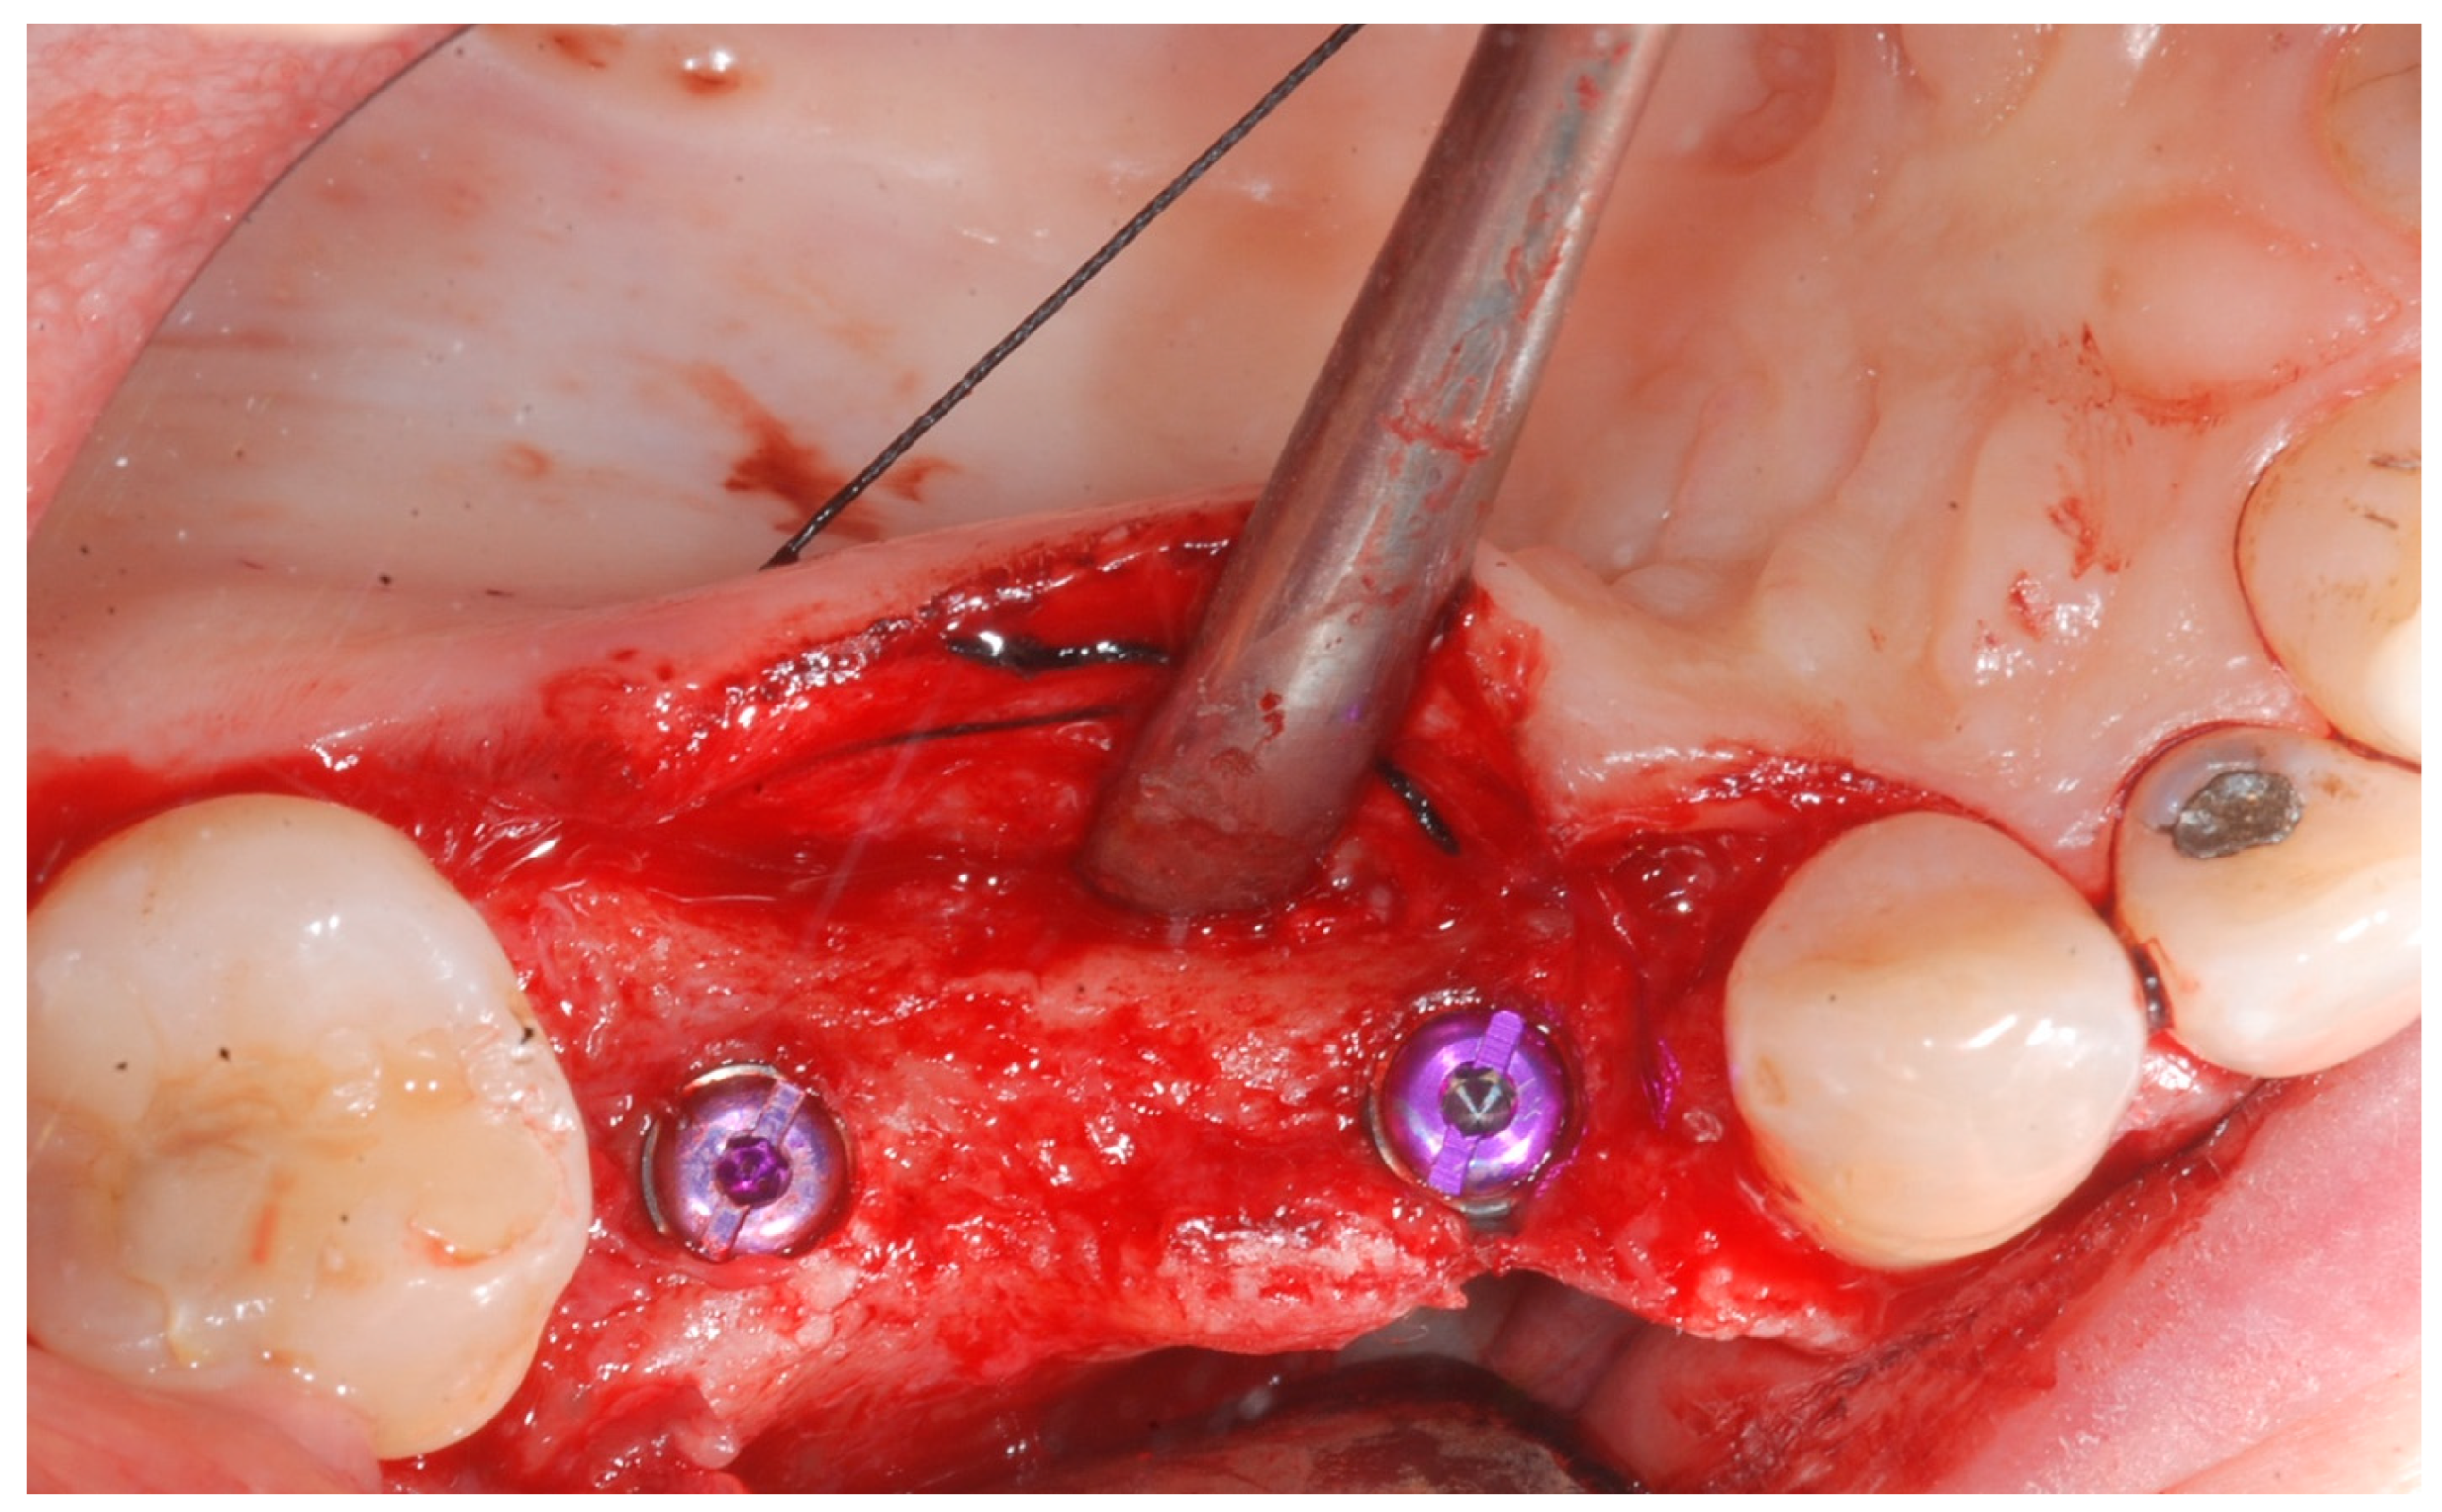

At this point, implants were placed according to the manufacturer’s instructions in a prosthetically ideal position with the aid of the surgical stent (Figure 3 and Figure 4).

Figure 4. Implant positioning and cover screws in place.